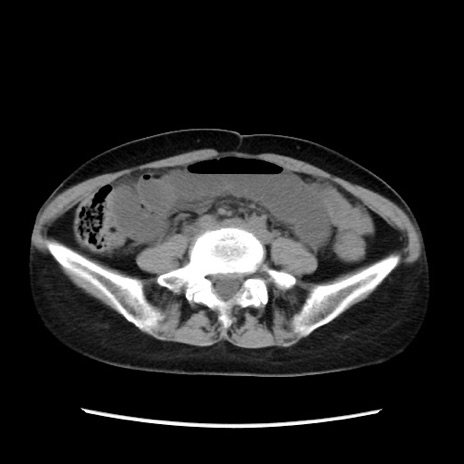

症例32(横断像)

【症例】40歳代 女性

【主訴】上腹部痛、嘔気・嘔吐

【現病歴】約9時間前頃から急に上腹部痛、嘔気、嘔吐が出現。改善しないため救急要請。

【既往歴】子宮頚癌(広汎子宮全摘術、放射線療法)、腸閉塞

【身体所見】腹部:平坦、軟、腸雑音亢進、上腹部を中心に腹部全体に圧痛あり。

【データ】WBC 8400、CRP 0.03